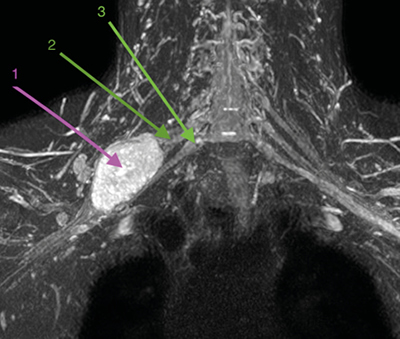

Figura 1

Figura 2